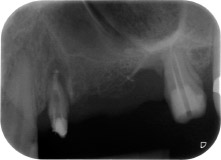

Einen Monat nach dem Eingriff waren sowohl die Schmerzen als auch die Entzündung an Zahn 24 minimal, die Zahnbeweglichkeit lag jedoch noch bei Miller-Klasse 2. Nach Freilegung und Reinigen des infizierten periapikalen und periradikulären Gewebes wurde das Ausmaß des Knochendefizits deutlich (Abb. 2 und 3).

An der bukkalen Wurzel fehlte der gesamte vestibuläre und distale Knochen. Das Attachment beschränkte sich weitgehend auf die palatinale Wurzel, was die anfängliche schlechte Prognose unterstreicht. Auch Zahn 27 wies ein verringertes horizontales Attachment (vgl. Abb. 12) und eine kleine apikale Aufhellung (Abb. 1) auf, allerdings ohne klinische Symptome.